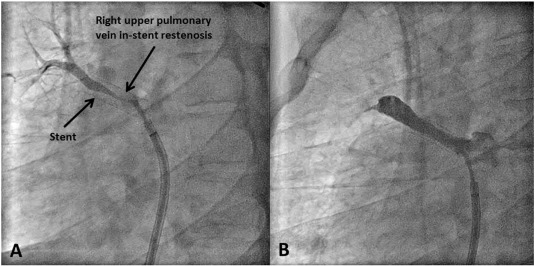

A 42-year-old male with FM and history of a left pneumonectomy presented with worsening hemoptysis and exercise intolerance over the last six months. CTA demonstrated high-grade stenosis of RUPV and chronic RMPV occlusion. Two stents were initially placed in the RUPV and in the next ten months, two more balloon angioplasties were performed for restenosis; despite this, the RUPV re-occluded (Fig. 3). Rotational atherectomy was then performed within the stent followed by cutting balloon angioplasty, but it resulted an acute in-stent thrombosis the next day. In the next eight months, the patient required three more angioplasties with cutting balloons as well as another stent in the RUPV. The patient is now being considered for a heart and lung transplant.

Right upper pulmonary vein stenosis requiring multiple interventions. (A) ...

Fig. 3.

Right upper pulmonary vein stenosis requiring multiple interventions. (A) Angiographic images showing in-stent restenosis (B) Angiographic images post-angioplasty.

Restenosis was the most common complication in our cohort. Among our cohort of eight patients, four developed restenosis. The 50% rate of restenosis observed in our cohort would still be an underestimation at the best, as two of the remaining four patients (case #1 and case #5) died shortly after the procedure. All four of these patients required repeat interventions and the total number of interventions ranged from 2 to 8. This is consistent with previous reports. Albers et al. reported that restenosis occurred in about 37% of their patients undergoing PV intervention with only 25% of them being symptomatic and requiring re-intervention [21]. Furthermore, the time to restenosis varied significantly from patient to patient. One extreme example is illustrated by case #6, in which eight separate interventions to the RUPV were required because of continued restenosis recurring over a period of 19 months, including cutting and standard balloon angioplasty, stent placement, and rotational atherectomy.

In-stent restenosis occurred in three of our eight patients and was treated with various techniques in each patient. In case #6, restenosis occurred after three separate interventions. Rotational atherectomy was used to treat complete occlusion of a PV stent but resulted in acute stent thrombosis requiring the use of an aspiration catheter. Additionally, cutting balloon angioplasty was also attempted in cases #6 and #8, but was met with limited success resulting in restenosis within two to four months. In case #7, in-stent restenosis occurred quickly within months of initial stent placement in the RUPV. In case #8, adjuvant therapy with oral sirolimus was tried, but restenosis still occurred in 7 months. Although rotational atherectomy and sirolimus were tried in two of our cases to treat restenosis, they were unsuccessful resulting in acute stent thrombosis and recurring stenosis respectively. We advise caution when trying these approaches in patients with FM and PV stenosis and suggest limiting their use to select patients with recalcitrant lesions.